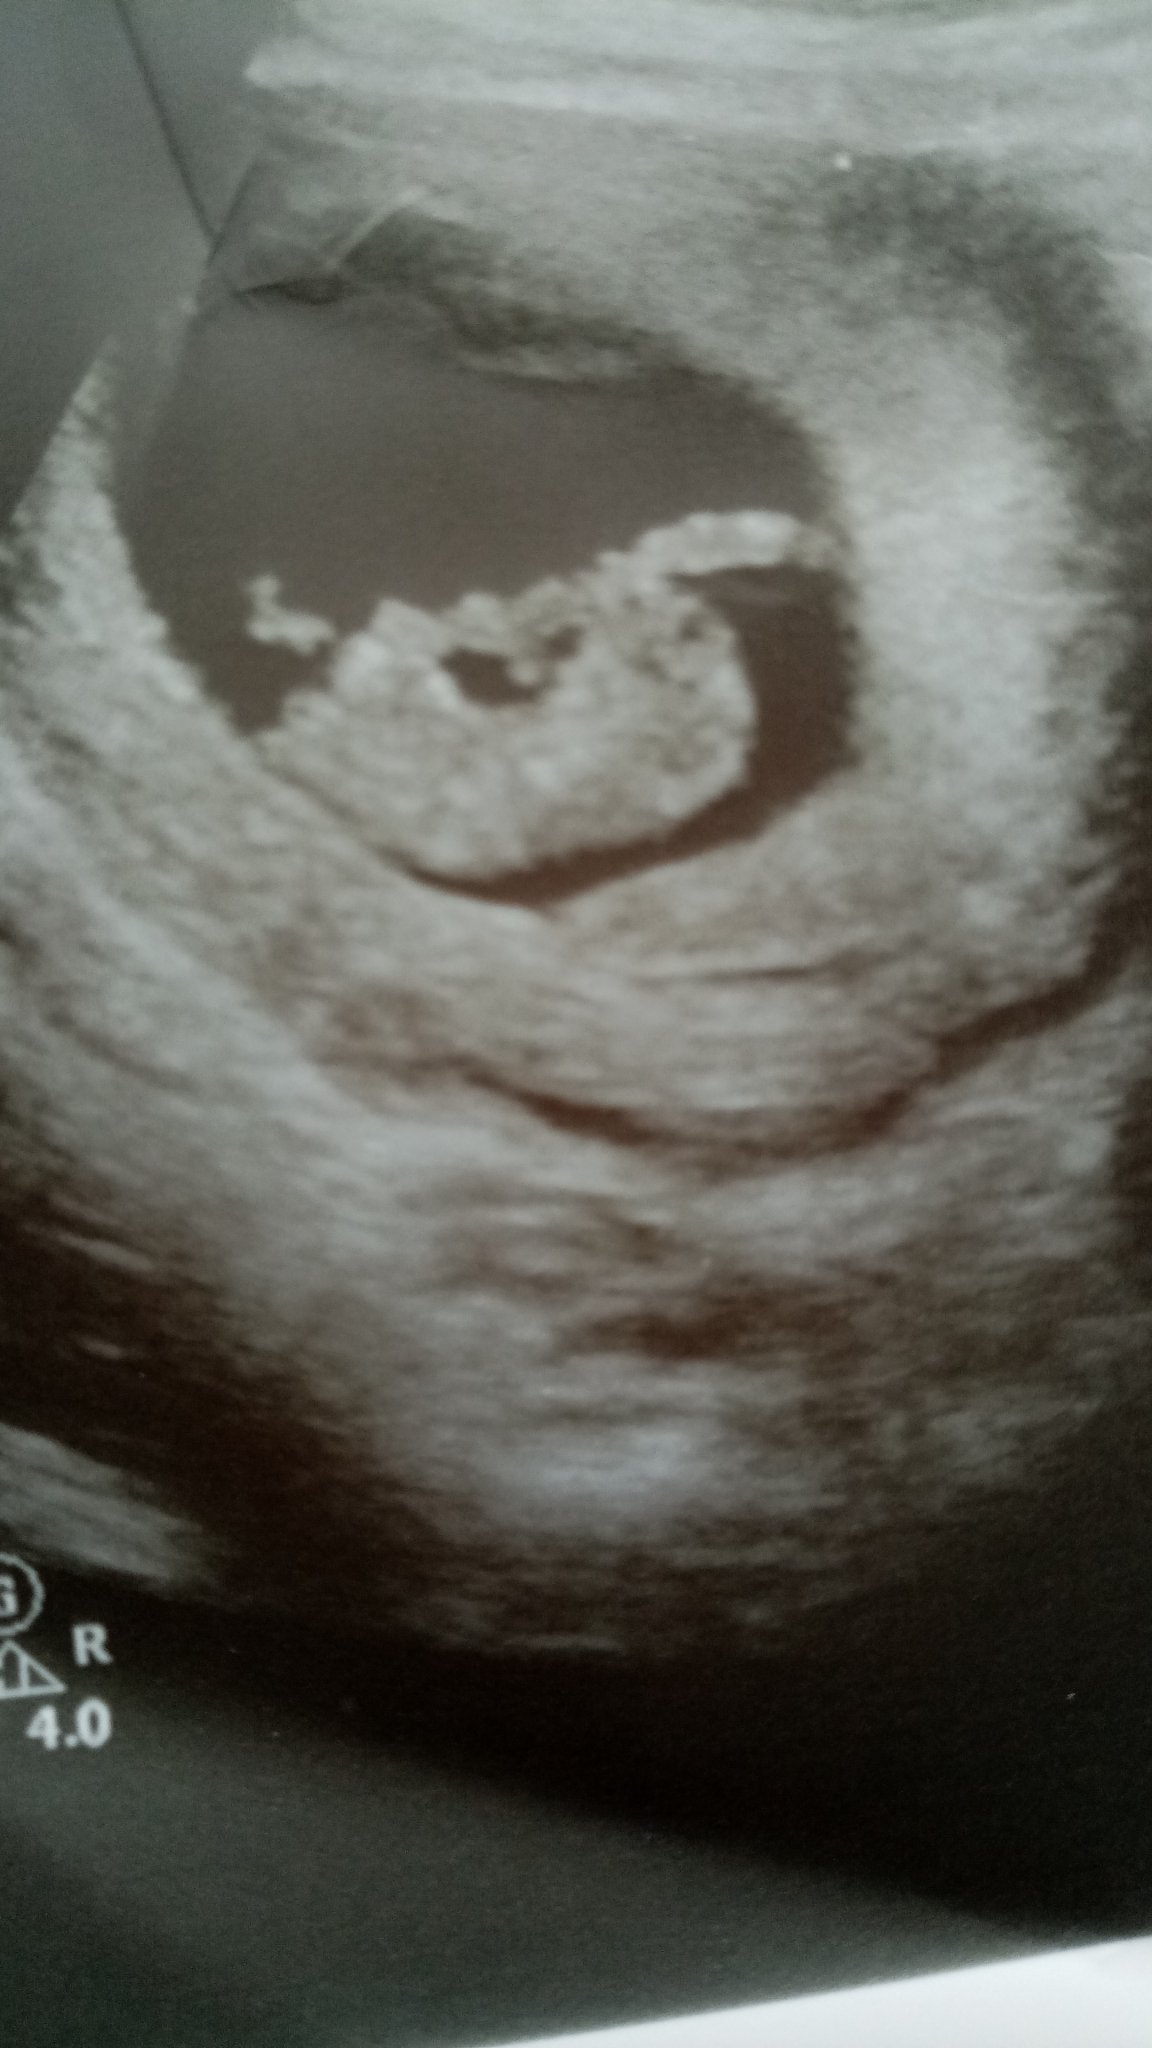

Видях бебето как риташе, много се впечатлих, невероятно.

На 35 съм, с първа бременност и поради този факт често се притеснявам за какво ли не.Stuck Out Tongue Winking Eye Вчера най-после си видяхме мъничето и чухме сърчицето и камък ми падна от сърцето.

Нямам търпение да го видя малчо, много време мина от 09.04. Тогава беше доста актино мъниче.